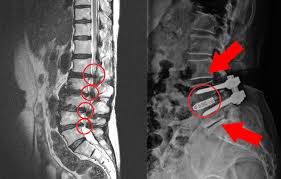

- MRI: 신경압박 정도, 협착 위치·범위 정확하게 파악

- CT: 골극, 척추관 협착 정도 상세 확인 가능

2) 수술적 치료

- 감압술: 신경을 누르는 구조물 제거

- 고정술: 불안정한 척추를 나사와 기구로 고정